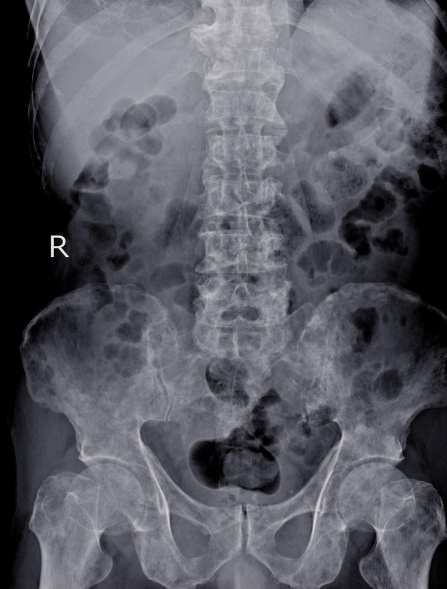

RADIOLOGÍA

Embárquese en este viaje educativo y conquiste el futuro de la radiología, donde el conocimiento avanzado se combina con la práctica , preparándolo para sobresalir en una carrera llena de oportunidades y logros.

El área de radiología, con docentes altamente calificados para brindarte lo mejor en esta nueva era de la inteligencia artificial y cómo cambia todo lo que sabemos del área, además de tener contenido de radiología, también habrá informática. x contenido de radiología para mantenernos actualizados en todo lo relacionado con PACS, HIS, LIS, RIS.